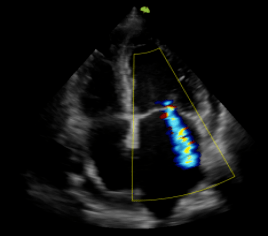

彩色多普勒血流显像显示舒张期二尖瓣口五彩射流束.

网易首页>正文申请入驻> pda的二维及彩色多普勒,频谱多普勒声像图大